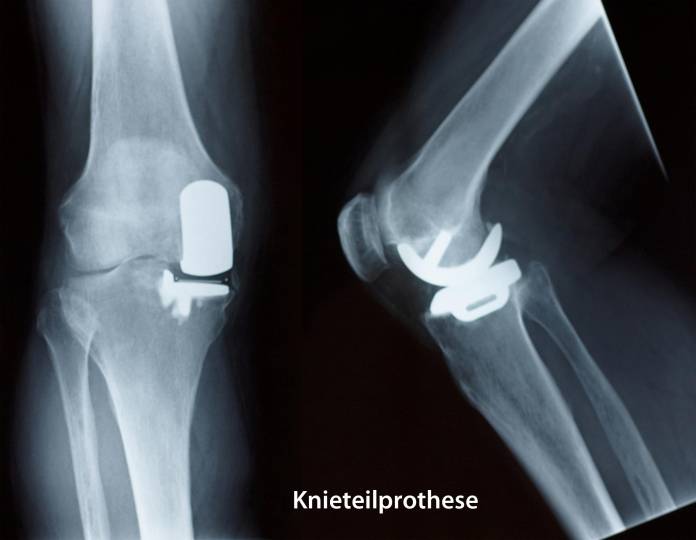

Eine Schlittenprothese kann minimalinvasiv (mit möglichst wenig Gewebeschädigung und kleinen Schnitten) eingesetzt werden. Hierbei werden jeweils eine Seite der Gelenkfläche am Oberschenkelknochen und die entsprechende Seite der Gelenkfläche am Unterschenkelknochen durch ein Metallimplantat ersetzt. Zwischen beide Metallkomponenten wird ein Kunststoff-Inlay eingebracht. Dieses ermöglicht ein weitgehend reibungsfreies Gleiten der beiden Gelenkpartner bei Bewegungen des Kniegelenkes. Eine Variante der Schlittenprothese besteht aus einem Metallimplantat am Oberschenkelknochen und einem Kunststoffanteil am Unterschenkelknochen. Nach diesem Prinzip funktioniert auch die Repicci-Prothese, welche eine besonders geringe Entfernung von Knochen erfordert.